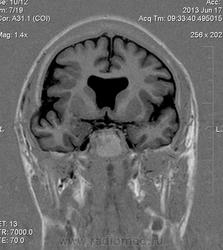

Мужчина 32 лет. Из анамнеза: перинатальное повреждение ЦНС, ДЦП, дизартрия, правосторонний верхний монопарез. С 16 лет приступы эпилепсии.

Аплазия прозрачной перегородки. Шизэнцефалия с открытыми краями в лобно-теменной области слева. Шизэнцефалия с закрытыми краями в лобной области справа? Утолщение коры по контуру расщелин и в области глазничной извилины правой лобной доли. Микрогирия? Гиперостоз костей свода черепа. Уважаемые коллеги, возможно я ошибаюсь, или есть еще аномалия?

сочетания отсутствия прозрачной перегородки и дисплазии ( разно степени выраженности) зрительных неровов  указывает на септоптическую дисплазию-нарушение развития в области средней линии , сопровождается мнггими другими структурными аномалиями, чаще шизэнцефалией.

На мой взгляд, полимикрогирия двусторонняя (конвекситальные отделы дорзальных отделов лобных долей и частично теменных, а также в базальном отделе полюса правой лобной доли) + закрытая шизенцефалия левой лобно-теменной области. Аплазия прозрачной перегородки (как признаки лобарной голопрозенцефалии).